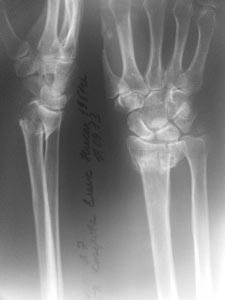

Перелом в "типичном месте" , Вопрос о фиксации шиловидного отростка

локтевой кости...

Оскольчатый перелом дистального метаэпифиза лучевой кости со смещением

отломков. Вопрос по поводу фиксации шиловидного отростка локтевой кости

Хотелось бы узнать мнения и аргументы. Надо ли фиксировать вообще?, если

да, то чем? и почему? Надеюсь на помощь коллег.